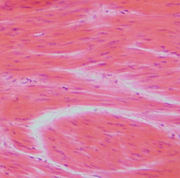

عضلة ملساء

العضلات الملساء Smooth Muscles في هذا الطراز تبدو الليفات العضلية غير مخططة ، ولهذا فهي تعرف بإسم العضلات الملساء ، كما توصف أيضا بأنها عضلات حشوية ، حيث إنها توجد في جدر الأوعية الدموية والأحشاء المجوفة ، مثل: القناة المعدية المعوية ، والمثانة البولية والرحم. وتعرف العضلات الملساء أيضا بأنها العضلات اللاإرادية ، حيث إنها ليست تحت سيطرة الإرادة ، وتخضع إنقباضاتها للجهاز العصبي الذاتي والهرمونات وظروف فسيولوجية أخرى.

تركيب الألياف العضلية الملساء

يظهر الفحص بالمجهر الضوئي أن الألياف العضلية الملساء تبدو في القطاعات العرضية كخلايا مغزلية الشكل ذات أطراف مستدقة. وللييفة العضلية الملساء نواة ممتدة أو بيضاوية الشكل ، تقع عند المركز في الجزء الأكثر سمكا من الليفة. وتحتوي النواة على نوية واحدة أو أكثر وحبيبات كروماتين دقيقة. ويتراوح طول الألياف العضلية الملساء من 20 ميكرومتر في جدر الأوعية الدموية الصغيرة إلى 200 ميكرومتر في الأمعاء ، إلى 500 ميكرومتر في رحم المرأة الحامل ، ويترواح قطرها ما بين 5-10 ميكرومتر.